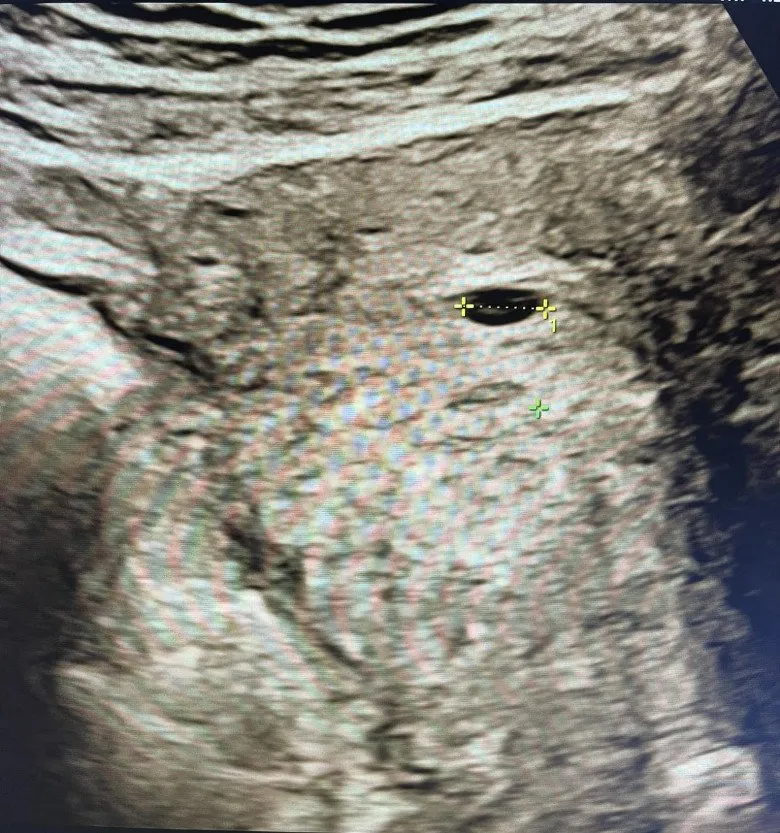

“Đi siêu âm nhưng chị khách hàng 48 tuổi này vẫn cứ khẳng định chắc chắn là chị không có thai được đâu. Bởi 2 tháng nay, vợ chồng chị mới gần gũi đúng một lần. Tuy nhiên khi siêu âm đã thấy chị có túi thai rồi”, bác sĩ Trường kể với Eva.

Theo đó, câu chuyện được bác sĩ Trần Đức Trường - bác sĩ siêu âm thai tại Bệnh viện Bưu Điện Hà Nội chia sẻ. Do bị trễ kinh 5 ngày, người phụ nữ quyết định đi thăm khám thì tá hỏa khi biết bản thân đã có thai. Thông tin này khiến người phụ nữ vô cùng bối rối, trong khi bản thân chị đã sẵn sàng tâm thế cưới vợ cho con và chuẩn bị lên chức bà, nhưng không ngờ cuối cùng chị lại chuẩn bị làm mẹ ở tuổi 48.